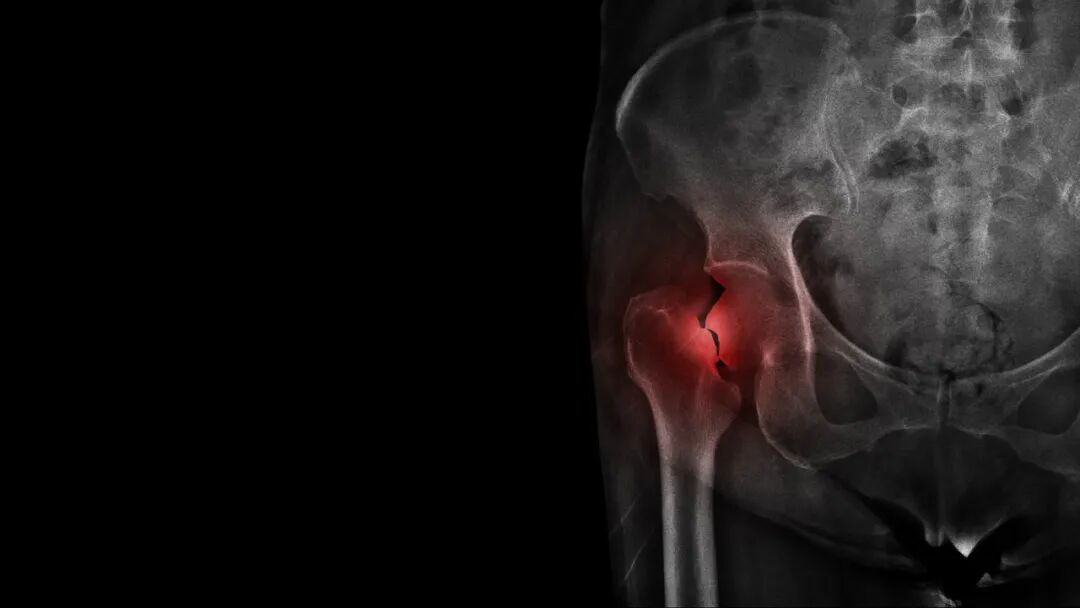

数据来源:《中国居民膳食指南》,制图:薛庆鑫这个时期钙摄入充足,可以增加骨矿含量、促进骨骼生长,有利于骨骼健康,同时也会直接影响到成年以后的骨骼健康。如果这个时期钙缺乏严重,不仅会影响身高还会增加成年后患骨质疏松的风险。因此,建议儿童和青少年一定要喝够奶。2. 更年期女性更年期女性内源性雌激素水平下降,不能抑制破骨细胞的作用,导致骨丢失加快,如果这期间钙摄入不足,将会增加患骨质疏松的风险,进而易发生骨折,严重影响女性的健康。早在 1984 年美国国立卫生研究院就召开了钙与骨质疏松的研讨会,将绝经女性钙的每日摄入量从 800 毫克/天提高到了 1500 毫克/天。我国《更年期健康管理核心信息专家共识》中提到:女性在更年期每日应保证钙摄入量 1000 毫克。而牛奶及其奶制品可以增加绝经后女性的骨密度,包括脊柱、股骨颈、髋骨及全身骨密度。3. 老年人随着年龄的增加,骨量流失加快,老年人患骨质疏松的风险显著增加。研究表明,2016 年我国 60 岁以上的老年人骨质疏松症患病率为 36%,其中男性为 23%,女性为 49%。可别小看了骨质疏松,这病也能“要命”。美国、欧洲和日本大约有 7500 万人患有骨质疏松,而病死率达到了 10%-24%,主要是髋骨骨折危害最大。

图库版权图片,不授权转载而且老年人胃肠功能下降、肝肾功能衰退、户外活动减少,这导致老年人需要摄入更多的钙,建议达到 1000 毫克/天。4. 高血压人群牛奶不仅可以补钙,也是补钾的好帮手。如果每天喝 300 克,就能摄入 540 毫克的钾,可满足一般人群每日钾需求量的 27%,对控血压有帮助。牛奶中的酪蛋白和乳清蛋白分解后产生的一些活性多肽结构,对降低血压有帮助作用;钙可以促进钠从尿中排泄,钙摄入量低会加强钠盐升高血压的作用,不利于控血压。另外,患有高血压疾病的人群普遍口味较重,平日盐摄入较多,高盐饮食会导致身体钙的流失增加。综合以上因素,建议高血压患者要重视牛奶的摄入。5. 高血糖人群2 型糖尿病的发生与生活习惯和饮食因素密切相关。目前认为牛奶中的钙、蛋白质及某些脂肪酸可以预防 2 型糖尿病。因为胰岛素的释放需要钙的参与,钙摄入不足将改变胰腺 β 细胞的细胞内和细胞外钙池中钙离子的平衡, 最终影响胰岛素的正常释放;乳清蛋白可以改善胰岛素抵抗。也有动物实验表明:充足的钙能够降低大鼠的体重、血清总胆固醇水平、并改善高胰岛素血症。另外,牛奶中的共轭亚油酸可明显改善大鼠的高胰岛素血症和高糖血症。因此,建议需要控血糖的人群多喝奶。6. 高尿酸人群尿酸过高会导致痛风发作,牛奶及其制品可起到预防作用。首先牛奶中的酪蛋白和乳清蛋白可以促进尿酸的排泄;其次奶制品可促进肾脏排泄尿酸前体黄嘌呤,在摄入牛奶 1-2 小时后黄嘌呤的排出量便大幅增加,可达 200%,这可能具有降尿酸的作用。另外,有研究显示:奶制品中特别是低脂奶可以降低尿酸水平。因此,高尿酸以及痛风患者可选择低脂奶。